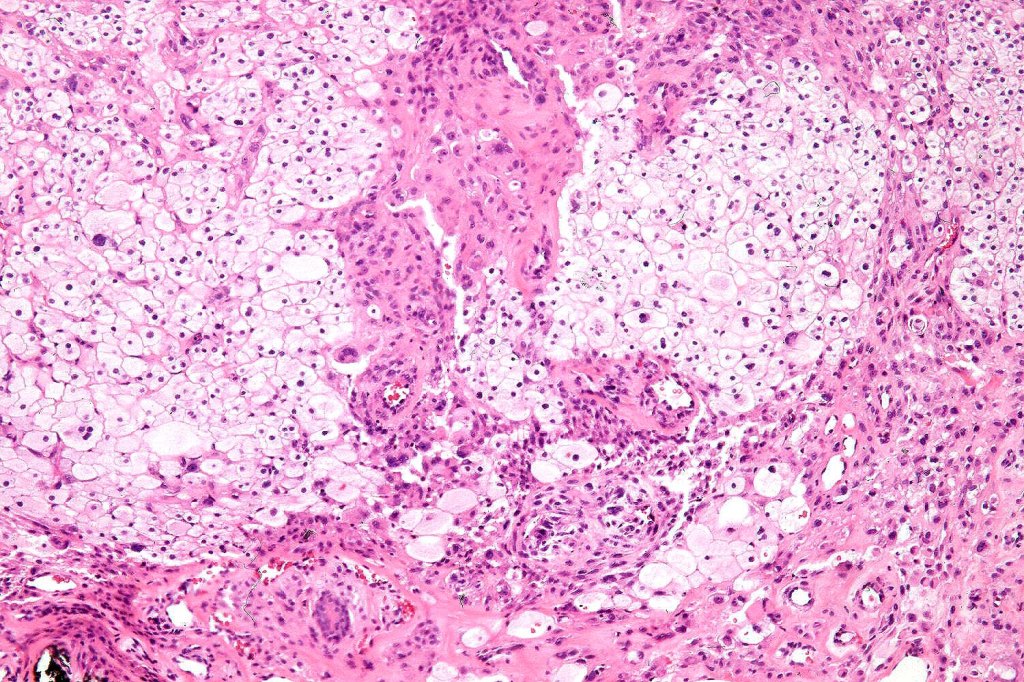

•Enlarged cells with copious eosinophilic, foamy or clear cytoplasm (some authors include melanoma with clear cell change in the same category)

•Variable pigmentation

•Nuclei vesicular or hyperchromatic

•Pleomorphism is not generally marked and indeed can be very subtle

•Variable mitotic activity

•DPAS granules

•Thought to be a result of abnormal or degenerative melanosome change